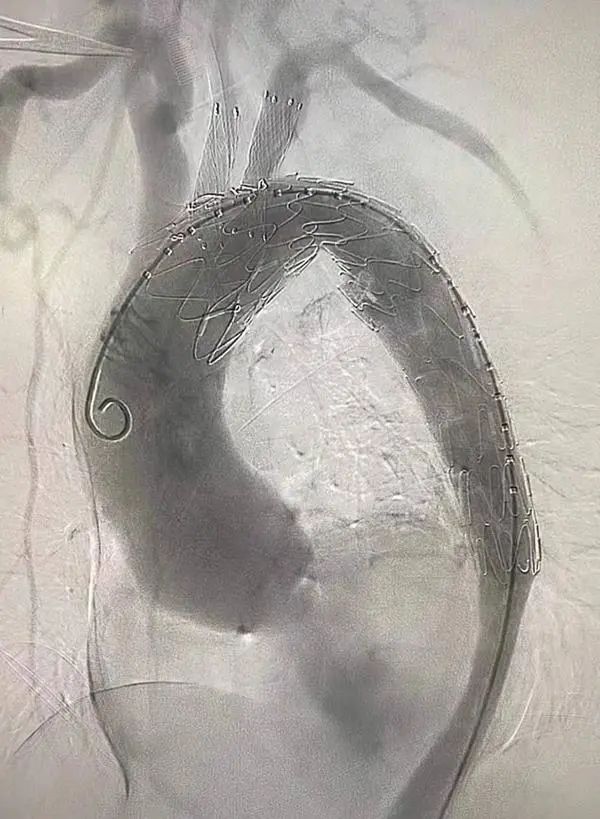

据介绍,这台手术对开窗位置提出了很高的要求。“我们需要在胸主动脉覆膜支架上开两个窗口,一个保证大脑的供血,一个保证胳膊的供血。”刘清泉说,他们运用3D打印技术实现了精准定位,通过术前反复模拟手术,可以大大提高成功率。

12月21日中午11时,手术正式开始。在南京鼓楼医院相关专家的指导下,在漯河市中心医院心内科、导管室、麻醉中心等多科室的通力合作下,刘清泉团队顺利完成了这例体外双开窗胸主动脉覆膜支架植入术,仅耗时2个小时。

“此前我们开展‘开窗支架手术’,最快也需要近3个小时,而体外开窗手术大大缩短了手术时间。”刘清泉说,除此以外,运用3D打印技术后,还具备了风险降低、花费降低、精准定位、提高成功率等优点。